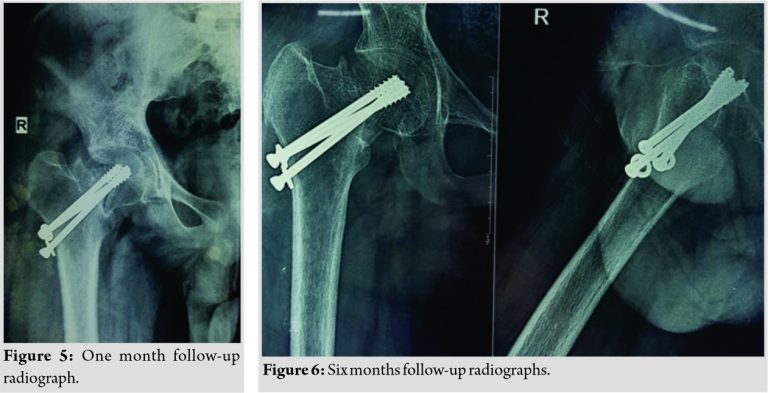

Post-operative radiograph showed good reduction on both views (Fig. 3). Post-operative period was uneventful. The patient was started on non-weight-bearing mobilization on the 2nd post-operative day. There were no complications. Range of movement exercises of the knee was started as the patient had arthrofibrosis of the right knee due to prolonged splinting. At the end of 6 weeks, the patient was started on partial weight-bearing as tolerated and then gently on full weight-bearing. He was also started on physiotherapy in the form of hip and back strengthening exercises at the end of 6 weeks. The patient resumed his daily work and had not faced any challenges. The patient had shortening of 1.5 cm of the right lower limb but was manageable with a shoe rise and has never been a concern clinically. Functional assessment was done using Harris Hip Score (Fig. 4) and was recorded at 6 weeks, 3 months, 6 months, 1 year, and 15 months follow-up. Radiologic assessment was done at the time of 1 month (Fig. 5) and until 15 months to check for fracture union and to rule out AVN of femoral head and implant loosening (Fig. 6, 7).